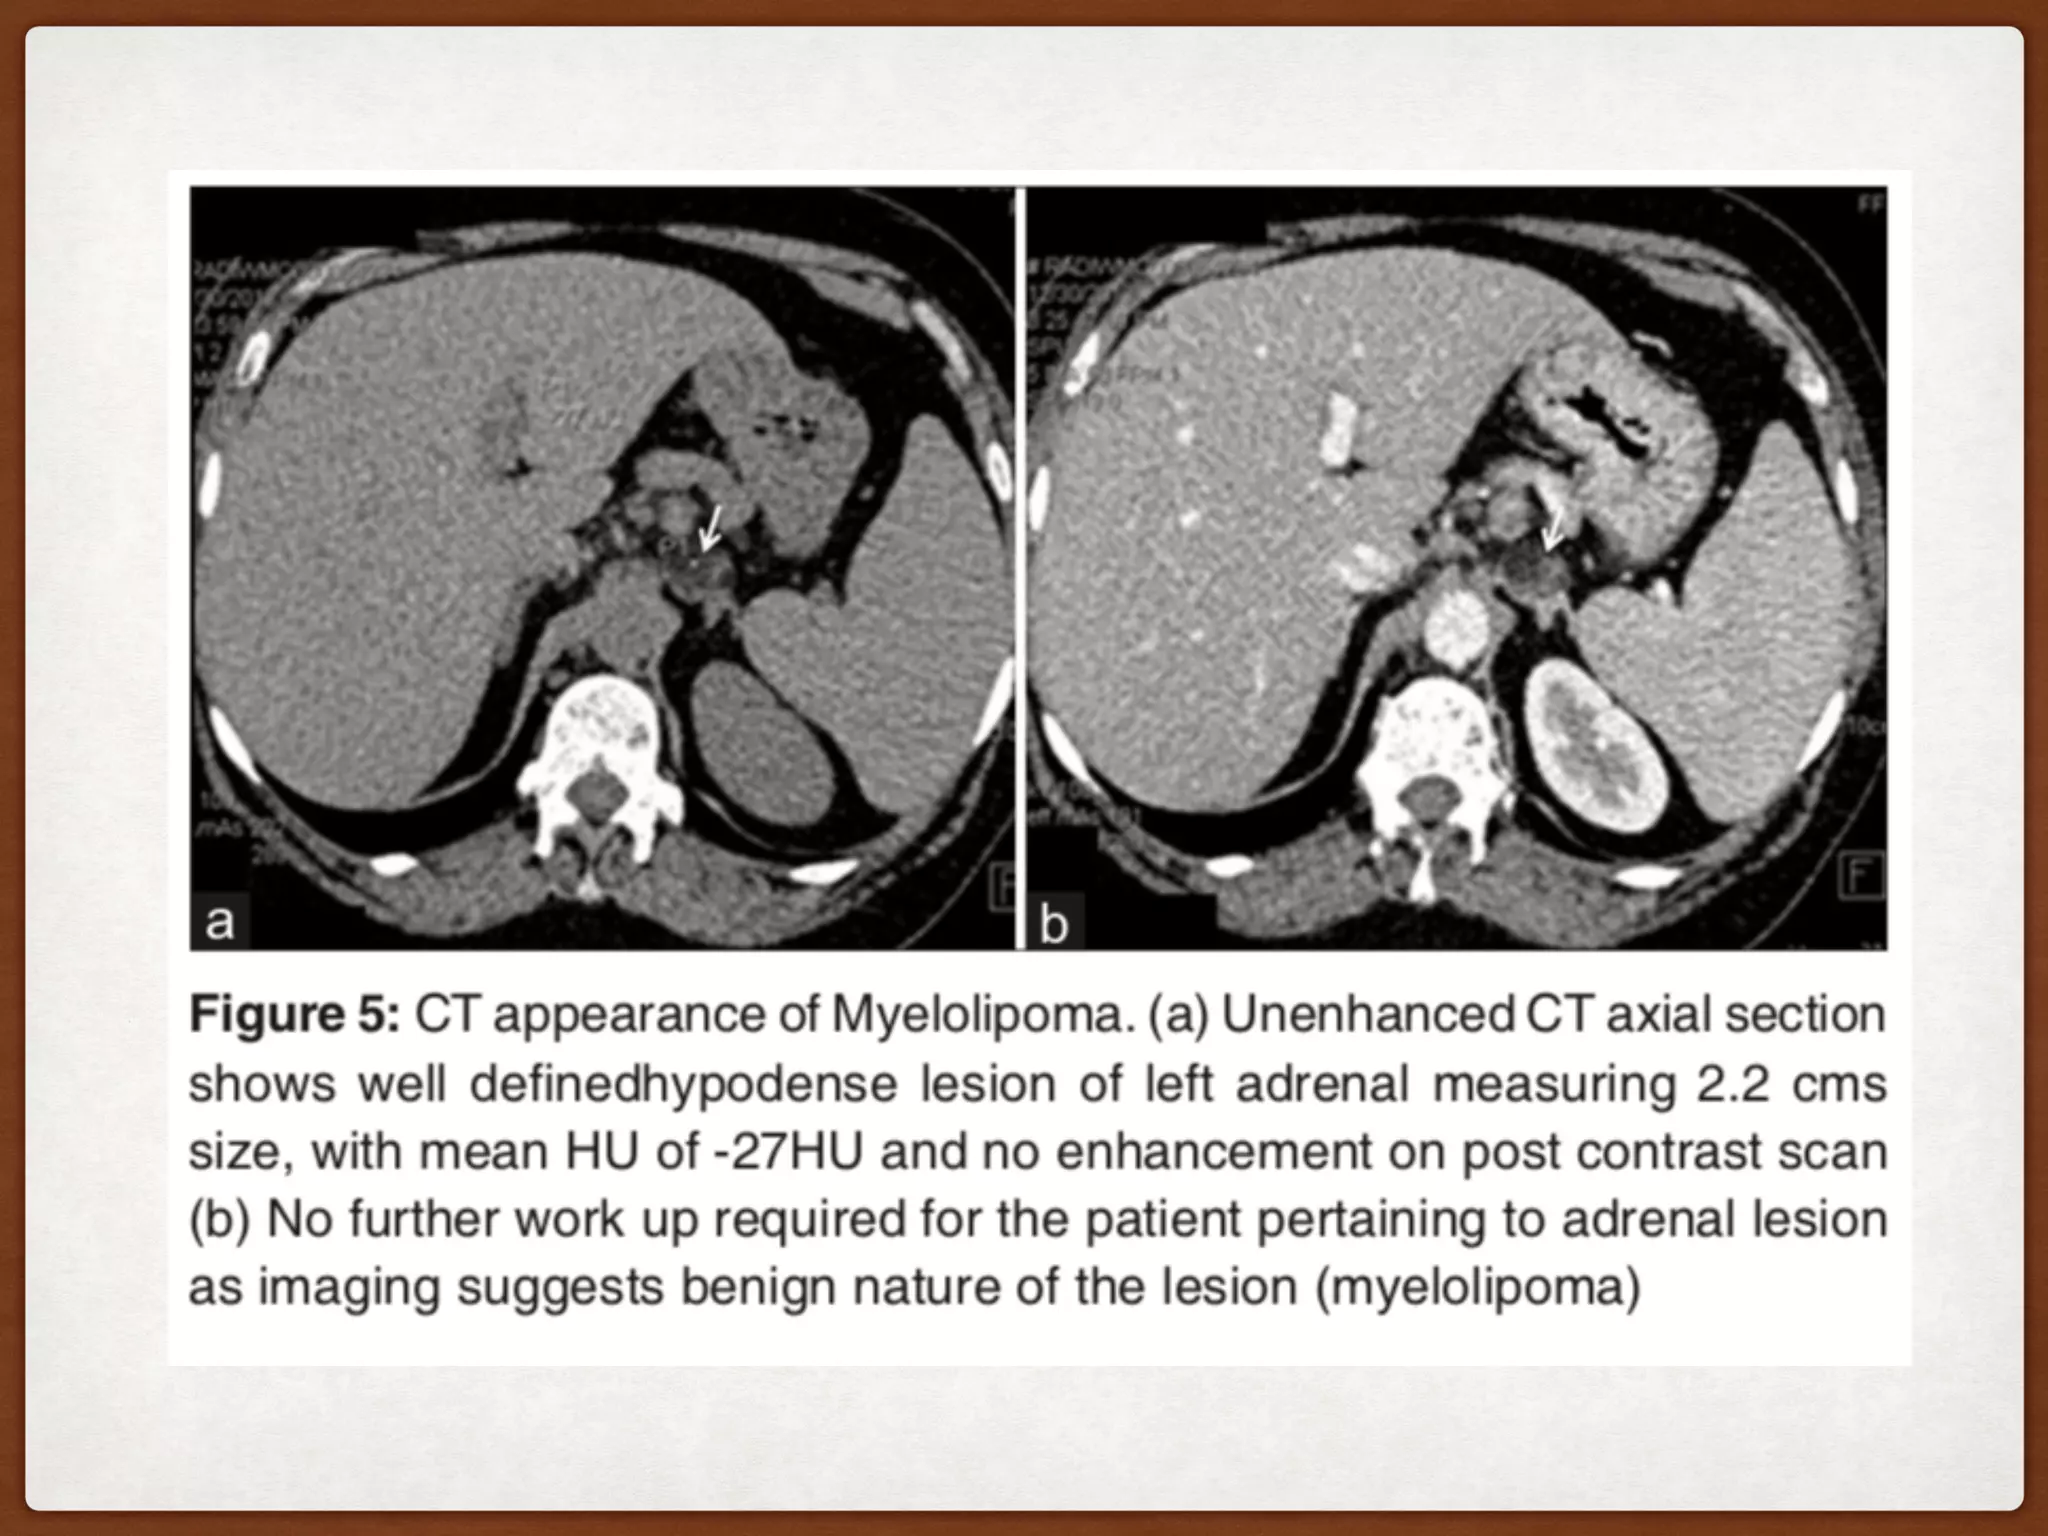

CT

The mass is usually relatively well circumscribed.

Larger leisions (typically >4cm).Nonenhancing.

The amount of fatty component is variable, ranging from

only a few small regions in an otherwise mostly soft

tissue density mass or masses made up of roughly equal

components of fat and soft tissue (50%) or almost

completely composed of fatty tissue.

Small punctate calcifications may be seen in 25-30% of

cases .

If haemorrhage is present then regions of higher

attenuation may be seen. This is more frequently

seen in large lesions (>10 cm) .